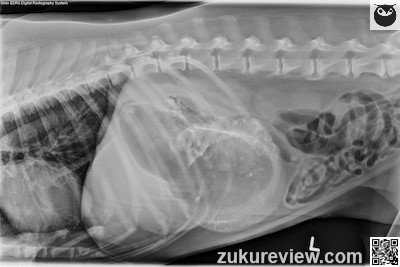

The stomach is markedly enlarged and filled with fluid and gas. There is mineral opacity material with a sharp edge in the body and pylorus.

There are small mineral opacities (gravel sign) in the dependent portion of the stomach. The enlarged stomach is causing a mass effect and displacing the other organs caudally, however peritoneal detail is good.

The radiographs show evidence of pyloric outflow obstruction such as a mass, stricture, polyp, or granuloma.